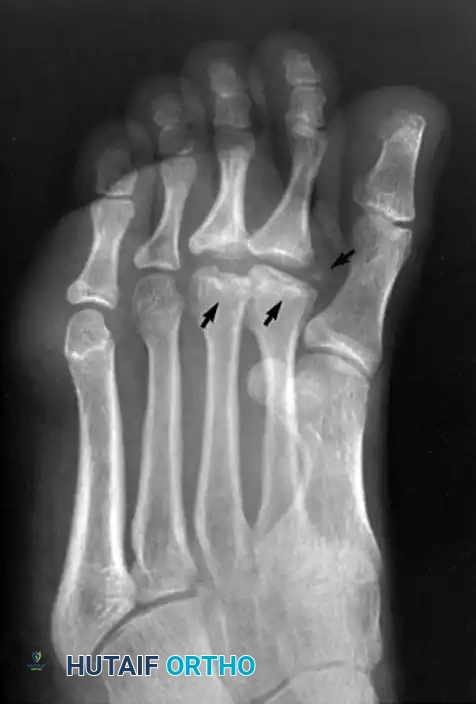

FIGURE 83-52 Freiberg infraction. Note flattening of second and third metatarsal heads and irregularity and separated bone fragment (arrows). (Courtesy of Steve Ikard, MD.)